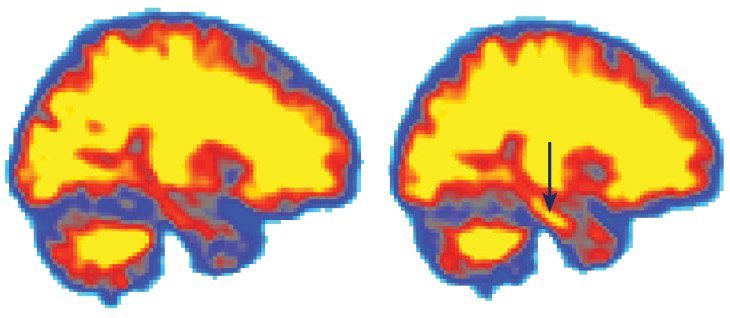

قام العلماء بتصوير دماغ متطوعّ بعد النوم ووجدوا كميات أقل للبروتين (يسار) . بالمقابل وجدوا تركيزات عالية منه في منطقة قرن آمون Hippocampus بالدماغ بعد حرمانه من النوم لمدة 31 ساعة (يمين).

استطاع العلماء أن يقيسوا مستوى مؤشرات بروتين الأميلويد Amyloid-Beta Markers لعشرين مشارك ومشاركة. تركيز البروتين بعد ليلة نوم هادئة (يسار) وليلة أخرى تمّ حرمانهم من النوم (يمين). معظم مستويات البروتين تتزايد بشكل ملحوظ مع اليقظة المستمرة كما هو موضح بالرسم البياني.